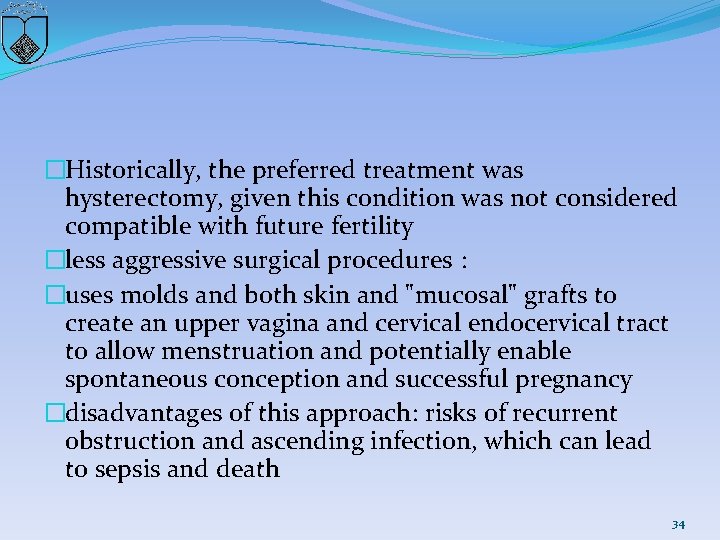

�Historically, the preferred treatment was hysterectomy, given this condition was not considered compatible with future fertility �less aggressive surgical procedures : �uses molds and both skin and "mucosal" grafts to create an upper vagina and cervical endocervical tract to allow menstruation and potentially enable spontaneous conception and successful pregnancy �disadvantages of this approach: risks of recurrent obstruction and ascending infection, which can lead to sepsis and death 34